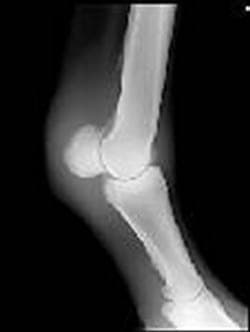

Nota: En esta serie de radiografías digitales, podemos apreciar las lesiones bien manifiestas en la articulaciones con patología de O.C.D.